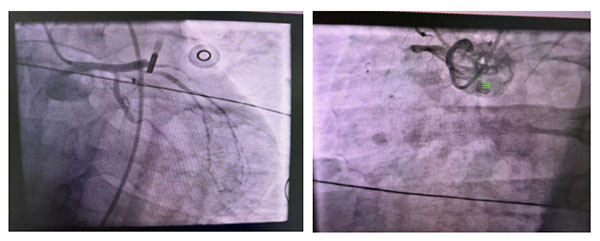

在机械辅助支持下,行急诊冠脉造影,确认三支闭塞,前降支近段急性闭塞,右冠近段慢性闭塞,回旋支远端慢性闭塞,优先开通前降支罪犯血管,导丝通过前降支,球囊扩张,快速植入1枚支架,血管开通后,血流恢复TIMI3级,恢复心肌血供,对其余慢性闭塞病变分次处理,避免长时间缺血再灌注损伤,血压维持在98/60mmHg,心率108次/分。

冠脉造影: